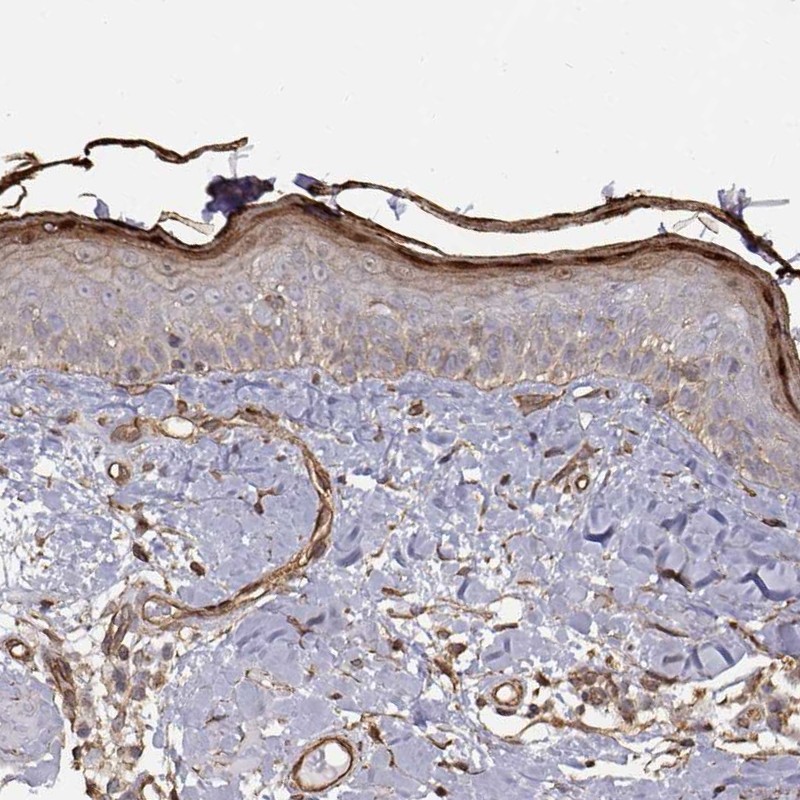

Immunohistochemistry analysis in human skin and pancreas tissues using Anti-GSDMA antibody. Corresponding GSDMA RNA-seq data are presented for the same tissues.